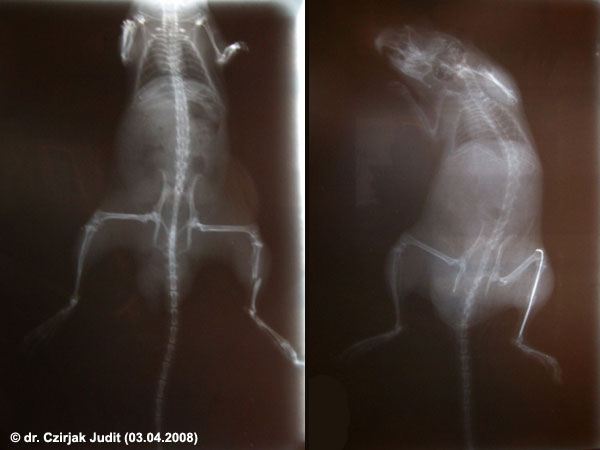

Cependant, une propriétaire de gerbille en Hongrie a pu faire opérer sa gerbille qui avait une fracture du tibia. Le médecin a implanté une aiguille de seringue (visible sur la radiographie illustrative) dans la patte afin de réduire la fracture en rapprochant les os brisés. Un mois plus tard, le chirurgien réopérait la bibille pour enlever l'attelle-aiguille. Après beaucoup de repos "Hektor" a récupéré :)

Merci à Judit Czirjak pour son aimable autorisation à publier cette anecdote et les radiographies de sa gerbille.